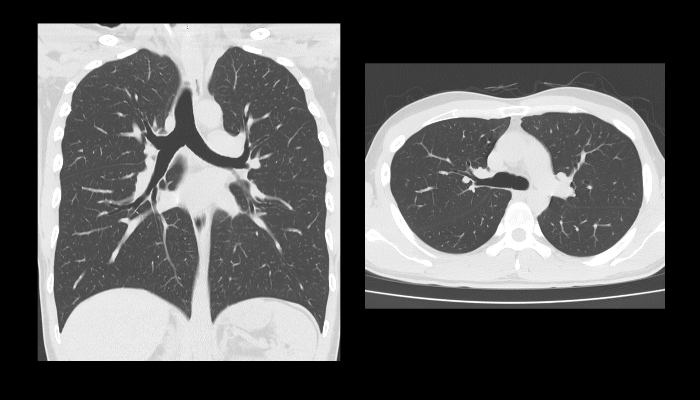

頭部CT画像 頭部CT脳出血や脳挫傷などの評価を行います。 胸部CT画像 胸部CT肺がんや肺炎や大動脈など胸部臓器を評価します。 心臓CT画像 心臓CT冠動脈を評価し、狭心症や心筋梗塞のリスクを検索します。 腹部CT画像 腹部CT肝臓・胆のう・膵臓・腎臓など腹部の重要臓器を評価します。 骨・関節CT画像 関節・骨CT骨折の評価に優れます。 動静脈CT画像 動脈・静脈CT動脈瘤や閉塞性動脈硬化症、深部静脈血栓症など血管の評価を行います。 大腸CT 大腸CT仮想内視鏡と言われる大腸の3D画像を得ることで苦痛の少ない大腸検査をすることができます。検査前日より検査食と下剤を服用していただきます。